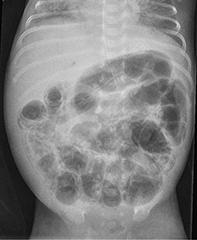

Necrotiserende enterocolitis Lees meer over Necrotiserende enterocolitis Necrotiserende enterocolitis

Necrotiserende enterocolitis (NEC) is een indrukwekkend ziektebeeld, dat in de neonatologie regelmatig voorkomt en waarvan de etiologie nog steeds niet helemaal duidelijk is. Er zijn wel factoren bekend die mogelijk een rol spelen, maar er zijn ook nog veel onduidelijkheden rondom dit ziektebeeld. NEC komt voornamelijk voor bij prematuren. De incidentie kan oplopen tot 7%. De mortaliteit ligt tussen 15 en 30% en is hoger naarmate de zwangerschapsduur korter is en het geboortegewicht lager.